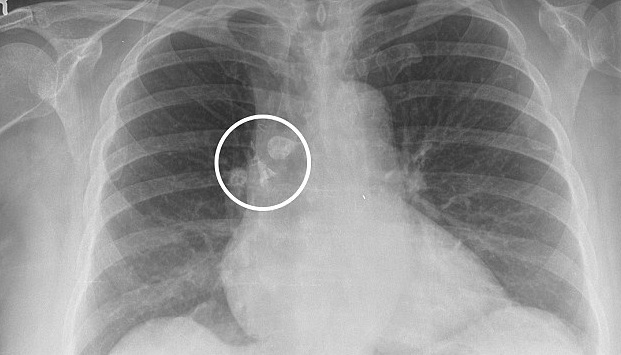

Se trataba de una extraña mancha en el pulmón derecho, inmediatamente los médicos le indicaron que eso era lo que ocurría cuando no se sacaba las joyas, puesto que dejan extrañas sombras en los exámenes. Bastante sorprendida la mujer les dijo que ella había seguido todas las instrucciones, por lo que ella sí se sacó su colgante.

Al escuchar esto, los especialistas comenzaron a revisar mejor los resultados y dieron con una lamentable noticia. La “sombra” que se veía en los exámenes se trataba de un tumor.